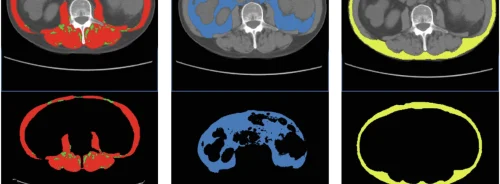

At the heart of healthcare’s most advanced ultrasound system is its UltraFast Imaging platform. This is currently the most sophisticated and speediest architecture on the market which acquires information 200 times faster than any other ultrasound system. The extreme velocity enables the company’s ShearWave Elastography scanning, the only real-time ultrasound imaging mode cleared by the FDA to measure and simultaneously display tissue stiffness in kilopascal, as well as UltraFast Doppler which speeds examination times and stands alone in its capabilities.

ShearWave Elastography (SWE™) is a non-invasive technique used by radiologists worldwide to visualise and quantitatively measure tissue stiffness across several organs in kilopascals. Assessing tissue stiffness is important, as stiffer tissue is more likely to be malignant. Furthermore SWE enhances the specificity of ultrasound alone, assisting physicians in their diagnostic and treatment process, to guide biopsies and monitory therapy.

Having proven itself clinically across multiple applications beyond breast, SWE has had a clear economic impact and has lead to a major change in patient management. Dr. James Trotter, MD of Baylor University Medical Center in Dallas, Texas explained that SWE was conducted in a manner identical to ultrasonography, making it a very comfortable and simple (less than 2 minutes) exam for the patient. He went on to say that it gives qualitative and quantitative ways to evaluate the degree of chronic liver injury our Hepatitis C patients and that it was used on a routine basis in the treatment determination process, allowing doctors to reduce the number of biopsies by roughly 50%.